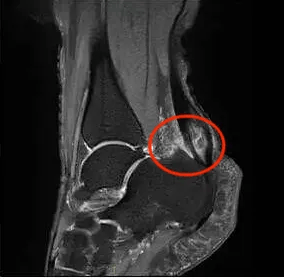

02 什么是Haglund畸形

Haglund畸形特指跟骨后上结节的异常骨性突起。这种结构性改变会导致:跟腱受到持续性机械刺激,滑囊受压产生炎症反应,最终形成跟腱止点病。

1. 骨突对跟腱及滑囊的反复挤压,引发:局部缺血,肌腱变性,滑囊炎